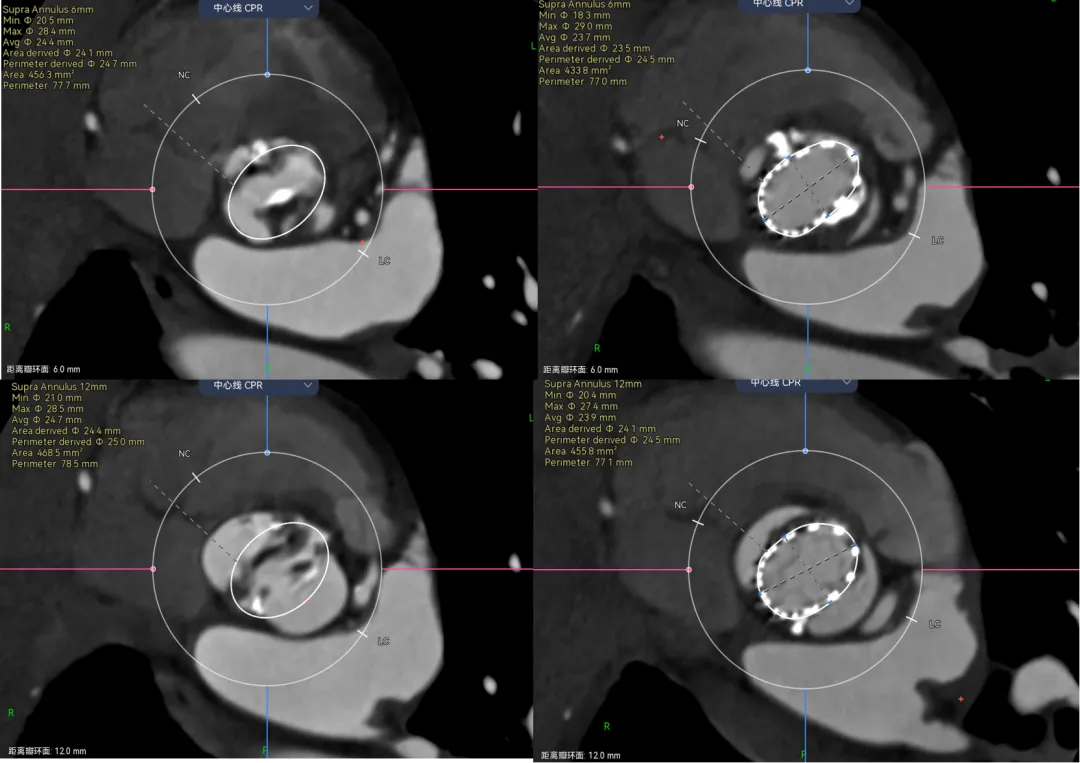

举个例子,病例-5,Type1的单边钙化,延伸到LVOT,瓣环这里笔者认为是因为把钙化避开的,因为他会对瓣膜有推挤作用。有些人则不会避开,这样瓣环会比预估的要大很多。

画法1-把钙化圈进去,瓣环径28。画法2-避开钙化,瓣环预估26.3,相差接近2mm。

那么这两种画法会对瓣膜型号选择造成很大的误判么?答案是不会,因为这个病人的限制在瓣上,你只能根据瓣上的空间来oversize,而且预估肯定会有点儿漏。

在看这个病例,三页瓣,RN、LR都有点融合。先看位置,融合会把瓣膜往左右交界的地方挤一挤。

再来看瓣上,你会发现我画的瓣上比真实的要大。这里就涉及到瓣膜的锚定区域了,我预估的瓣上如果瓣叶打开可能会是直径在25mm左右,但是真实瓣膜的尺寸如果在这个位置,他只有22左右。所以瓣上是没有办法提供锚定的,只能卡在瓣环。

可以看到,瓣膜放进去23的区域正好对应该型号瓣膜尺寸。